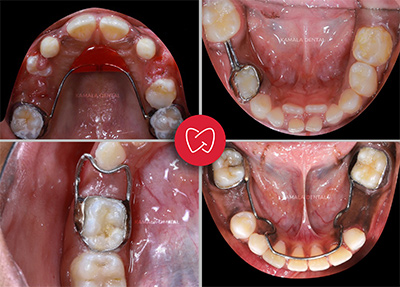

- Space Maintainers: Provided when milk teeth are lost prematurely to preserve the space for proper eruption of permanent teeth.

- Habit Breakers: Custom appliances used to correct thumb sucking, tongue thrusting, and mouth breathing habits, helping prevent future misalignment of permanent teeth.